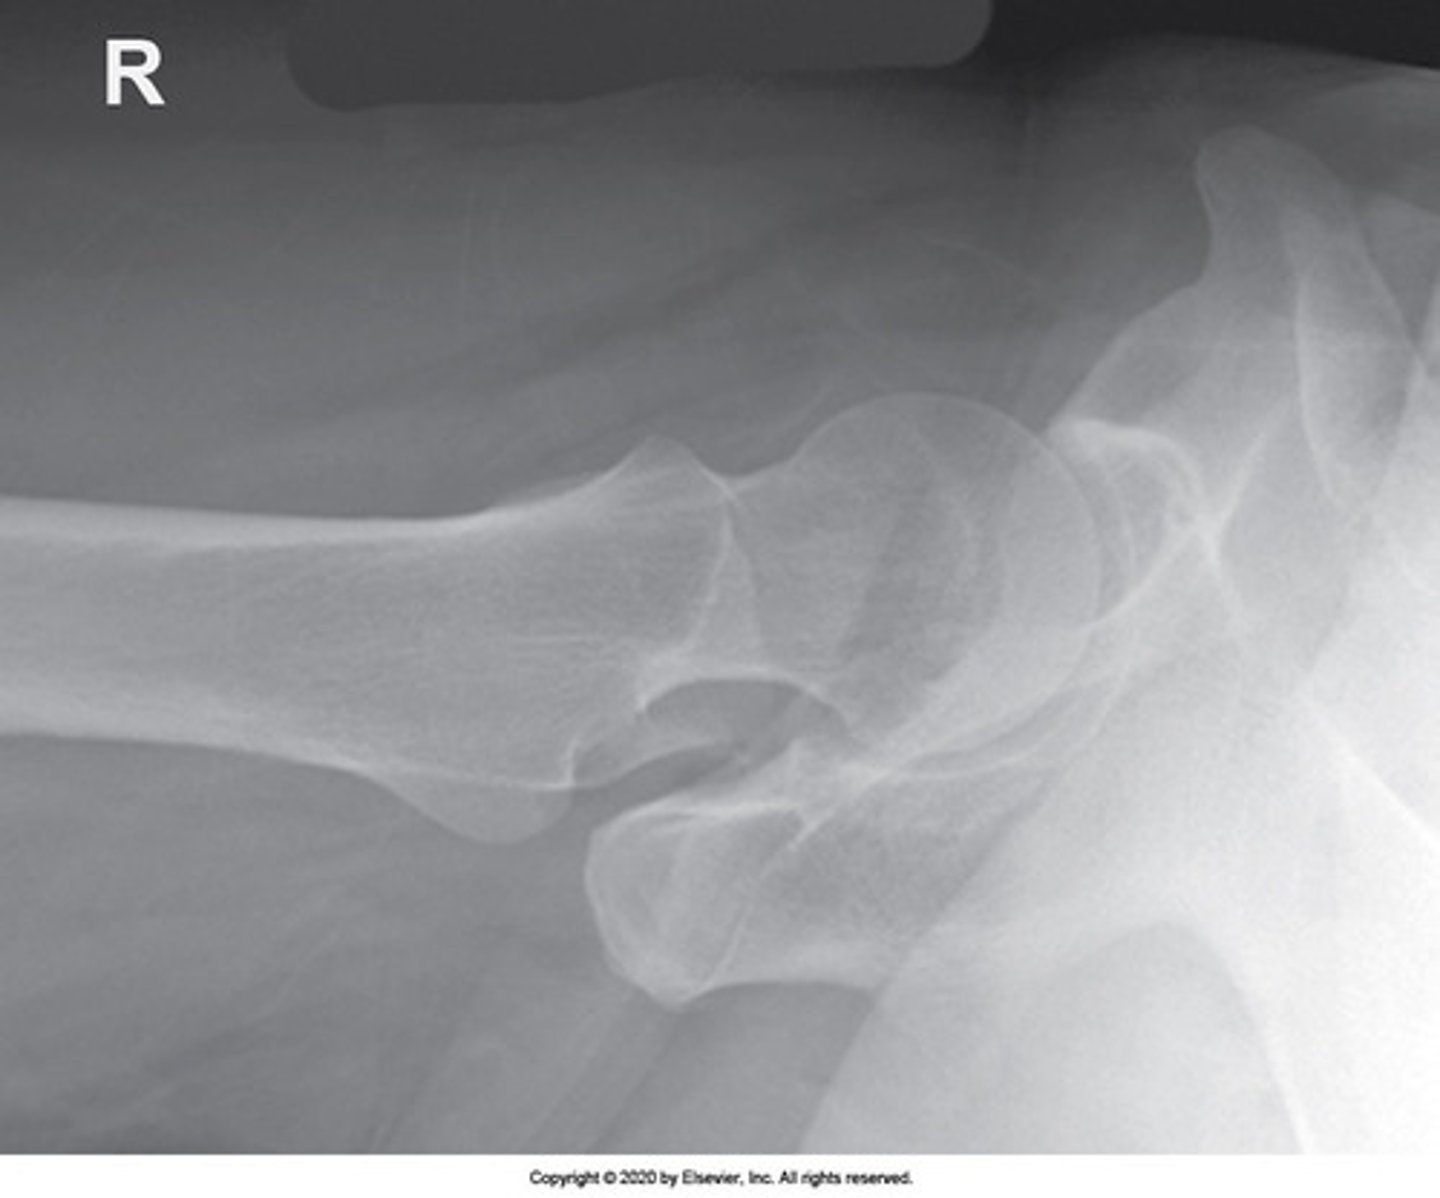

Identify the projection:

AP Hip

Axiolateral Hip (Danelius-Miller)

AP oblique hip (Modified Cleaves)

Lateral hip (Lauenstein)

IA Positioning: Lateral Hip (Lauenstein Method)

- femur is parallel to IR

- femoral neck is super-imposed by greater trochanter